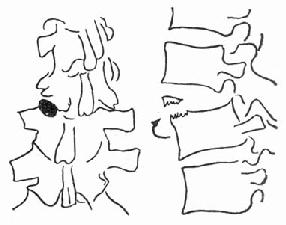

(一)压缩骨折 前屈或侧屈暴力引起,最常见的为椎体前缘高度减少的前方楔伏骨折(图73-1)。此外还有侧方压缩骨折,即椎体两侧高度不一样。这些楔伏改变常伴有椎体终板的损伤及椎间盘的损伤,椎间盘可被压进椎体内。但压缩骨折的椎体后缘高度不变,有别于爆裂型骨折。

图73-1 前方压缩骨折

(二)旋转损伤 X线检查可见一个椎体在另一个椎体上旋转(图73-2)。有时可见椎间隙变窄,主要为纤维环及髓核损伤。下一个椎体的前缘上角,可被纤维环撕脱一小片,但椎体高度不变。少数仅有单纯椎间隙变窄,无纤维环撕脱。

图73-2 脊柱旋转损伤